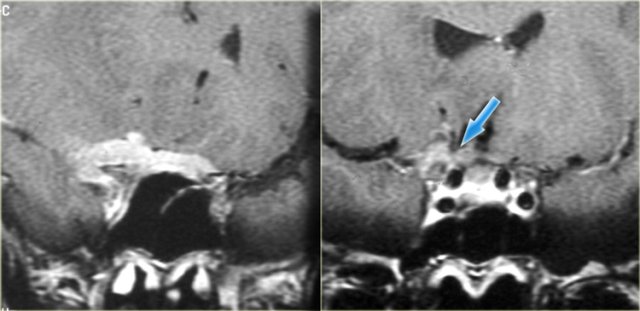

On the left a patient who had a prior cranio-facial resection (yellow arrows) for an undifferentiated carcinoma.

This patient was treated with chemoradiation.

The T2WI on the left shows tumor recurrence intracranially.

Continue with the contrast enhanced images.

Recurrence of carcinoma with dural implants bilaterally Recurrence of carcinoma with dural implants bilaterally

In cases like this a recurrence tend to show bizarre patterns such as these extensive dural implants.